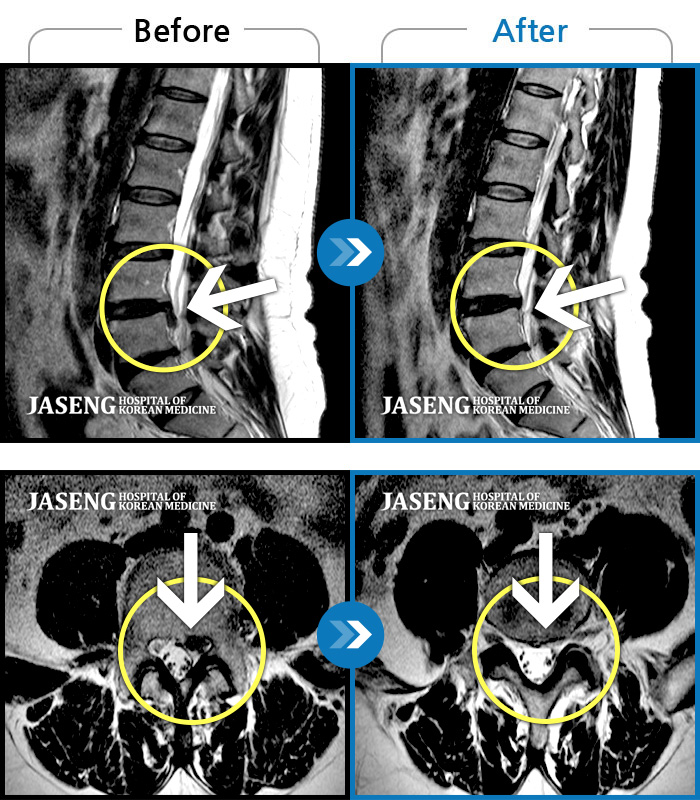

저는 협착증으로 병원에 입원해서 원장님께 치료 받고 있는 환자에요~

입원 전에는 다리가 저리고 땡겼는데 지금은 저림 증상은 거의 사라졌답니다

다 원장님 덕분이에요~~^^